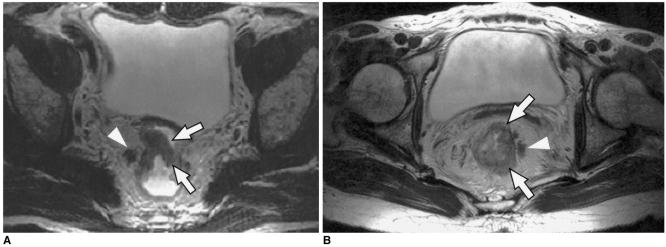

To determine the utility of MR imaging in evaluating the prognostic factors for a local recurrence of rectal cancer following a curative resection.

The preoperative MR images obtained from 17 patients with a local recurrence and 54 patients without a local recurrence, who had undergone a curative resection, were independently evaluated by three radiologists. The following findings were analyzed: the direct invasion of the perirectal fat by the primary rectal carcinoma, involvement of the perirectal lymph nodes, perirectal spiculate nodules, perivascular encasement, and an enlargement of the pelvic wall lymph nodes. The clinical and surgical profiles were obtained from the patients' medical records. The association of a local recurrence with the MR findings and the clinicosurgical variables was statistically evaluated.

RESULTS

Of the MR findings, the presence of perivascular encasement (p = 0.001) and perirectal spiculate nodules (p = 0.001) were found to be significant prognostic factors for a local recurrence. Of the clinicosurgical profiles, the presence of a microscopic vascular invasion (p = 0.005) and the involvement of the regional lymph nodes (p = 0.006) were associated with a local recurrence. Logistic regression analysis showed that the presence of perirectal spiculate nodules was an independent predictor of a local recurrence (odds ratio, 7.382; 95% confidence interval, 1.438, 37.889; p = 0.017).

The presence of perirectal spiculate nodules and perivascular encasement on the preoperative MR images are significant predictors of a local recurrence after curative surgery for a rectal carcinoma. This suggests that preoperative MR imaging can provide useful information to help in the planning of preoperative adjuvant therapy.